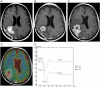

We examine the role of dynamic susceptibility contrast (DSC) magnetic resonance imaging (MRI) perfusion in differentiating pseudoprogression from progression in 20 consecutive patients with treated glioblastoma. MRI perfusion was performed, and relative cerebral blood volume (rCBV), relative peak height (rPH), and percent signal recovery (PSR) were measured. Pseudoprogression demonstrated lower median rCBV (P=.009) and rPH (P<.001), and higher PSR (P=.039) than progression. DSC MRI perfusion successfully identified pseudoprogression in patients who did not require a change in treatment despite radiographic worsening following chemoradiotherapy.